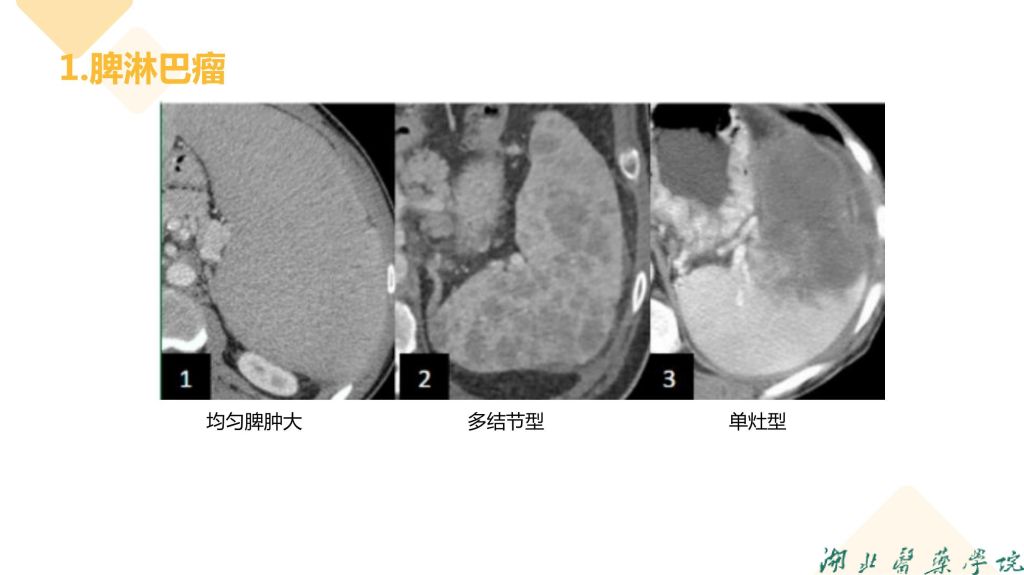

病例分享-脾脏实质性占位性病变